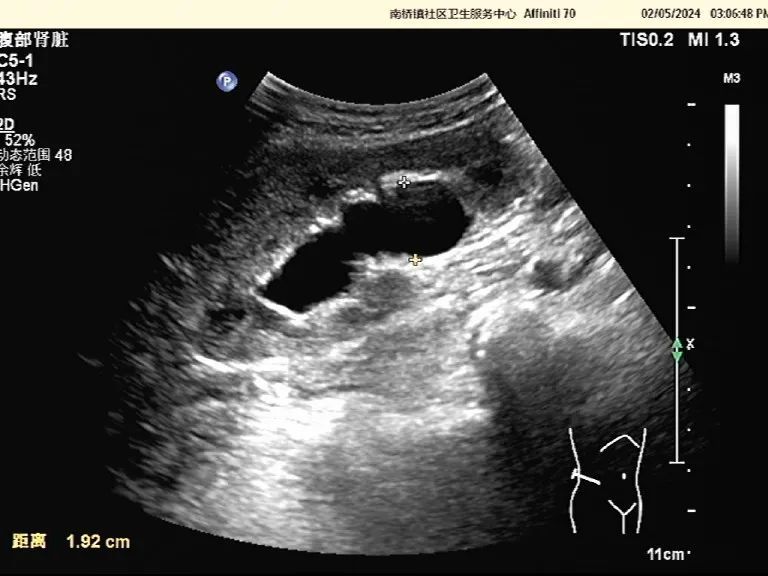

时间追溯到2024年2月5日,超声科一如既往地忙碌,周阿姨走进诊室,刚躺下就开始说她的情况:“蒋医生,我血尿有一段时间了,上个月住院治疗一周,也没有得到改善,你再帮我仔细查查,我到底有什么问题?”周阿姨的语气中充满了忧虑,蒋医生一边安抚周阿姨紧张的情绪,一边帮她做检查。检查中,蒋医生发现周阿姨的右肾积水,右侧输尿管上段扩张,但并没有探查到肾结石的迹象,结合周阿姨有血尿的病史,她便向周阿姨解释:“阿姨,你这个情况,我建议你需要进一步检查,你的右肾积水,右侧输尿管上段扩张,并伴有不明原因的血尿,是需要警惕的,要去查明原因,不能掉以轻心!”